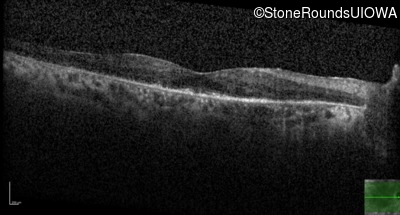

Age at visit: 53 years

OD OS

This 53 year old woman first came to attention when she had difficulty walking down stairs. A few years later she noticed difficulty seeing in dim light.